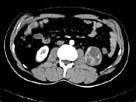

问题 女,63岁,左腰部隐痛不适1个月余,CT平扫+增强如图所示,下列哪项诊断正确 ( )

选项 A、左肾下极脓肿 B、左肾下极淋巴瘤 C、左肾下极错构瘤 D、左肾下极癌 E、左肾下极囊肿

答案 D